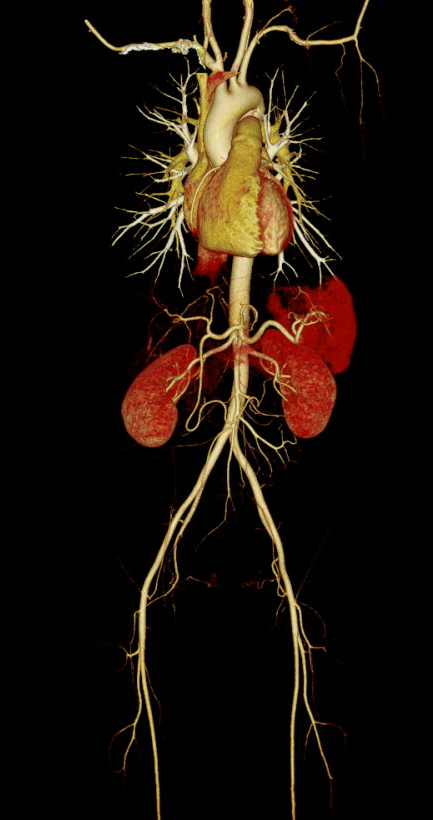

大范围低剂量CTA成像

采用业内最先进液态金属轴承技术的超大热容量球管,结合独有的低千伏、低毫安成像模式,天河640可实现冠脉、主动脉、下肢动脉等全身各部位大范围扫描、微辐射剂量的检查。低千伏扫描模式有效降低辐射剂量、对比剂总量、对比剂浓度、对比剂注射速率,降低肾功能不全受检者增强检查风险、减少对比剂外渗风险、并可大幅度提升增强检查碘对比剂对比度,提升强化效果;同时,系统还可根据不同患者体型和扫描协议自动推荐扫描管电压,在降低患者扫描剂量的同时,优化对比度噪声比。

联影ct怎么样科技助力健康丨“全球顶尖超高端”联影天河640层CT启用“满百天”_https://www.jmylbn.com_新闻资讯_第13张

联影ct怎么样科技助力健康丨“全球顶尖超高端”联影天河640层CT启用“满百天”_https://www.jmylbn.com_新闻资讯_第14张

图片说明:肺动脉+主动脉全程+下肢动脉大范围一次扫描成像。